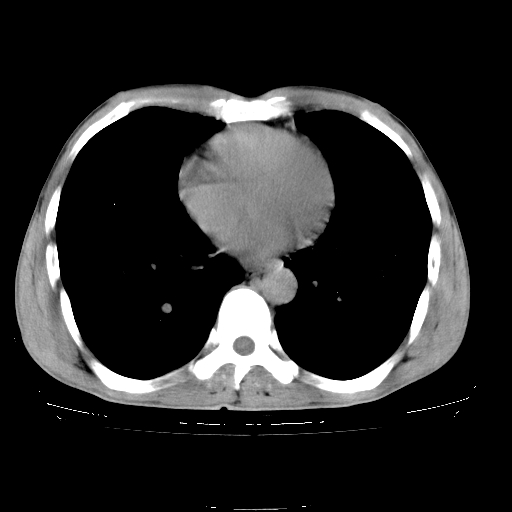

以下是引用yangyudong333在2008-4-29 5:38:00的发言:[br]比较典型的矽肺结节.支持[br]诊断依据:[br] 1.x线表现:[br] ①典型矽肺为多发直径 1~3mm 小结节,即矽结节,由胶原纤维和硅尘构成,可融合成团块,好发于上肺。[br] ②团块周围常有肺大泡。[br] ③胸内淋巴结增大、钙化。如肺门淋巴结呈蛋壳样钙化有助于与其他尘肺区别。[br] ④胸膜常广泛粘连、增厚。[br] 2.ct表现[br] ①两肺散在大小较为一致的小结节影,其密度较高,边界清楚。[br] ②小结节可融合为较大团块影,直径约 1cm ,甚至可达 10cm以上,易发生在上叶。[br] ③小结节周围常并有小叶中心气肿或弥漫性肺气肿。

以下是引用liuyue在2008-4-28 22:30:00的发言:[br]比较典型的矽肺结节.[br]请结合临床及化验除外矽肺合并肺结核之可能.